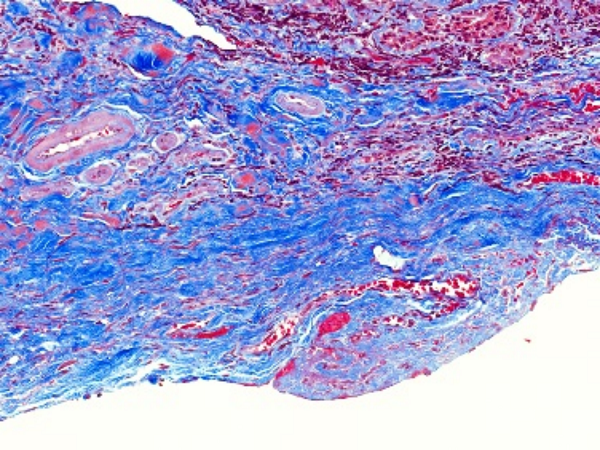

Masson染色是一种用于显示组织中纤维成分的特殊染色方法,主要用于区分胶原纤维和肌纤维,在病理学和组织学研究中有广泛的应用。**一、染色原理**1. 试剂作用 - **酸性复红**:它是一种酸性染料,能够将细胞质、肌纤维等染成红色。在染色过程中,酸性复红与肌纤维中的碱性蛋白结合,使肌纤维呈现出红

4008386992 立即咨询Masson染色是一种用于显示组织中纤维成分的特殊染色方法,主要用于区分胶原纤维和肌纤维,在病理学和组织学研究中有广泛的应用。

**四、结果观察与分析**

1. 细胞核

- 经过Weigert铁苏木精染液染色后,细胞核呈现黑色。可以观察细胞核的大小、形状、位置以及核内结构(如核仁),这有助于判断细胞的类型和状态。

2. 肌纤维

- 被酸性复红染色后呈红色,通过观察肌纤维的分布、走向和形态,可以了解肌肉组织的结构和功能。例如,在心肌组织中,心肌纤维呈分支状,相互连接成网状;在平滑肌组织中,肌纤维呈长梭形,排列较为规则。

3. 胶原纤维

- 被苯胺蓝染色后呈蓝色。可以观察胶原纤维在组织中的分布和含量,这对于研究组织的纤维化程度、创伤修复等过程具有重要意义。例如,在肝脏纤维化的组织中,会出现大量蓝色的胶原纤维增生。